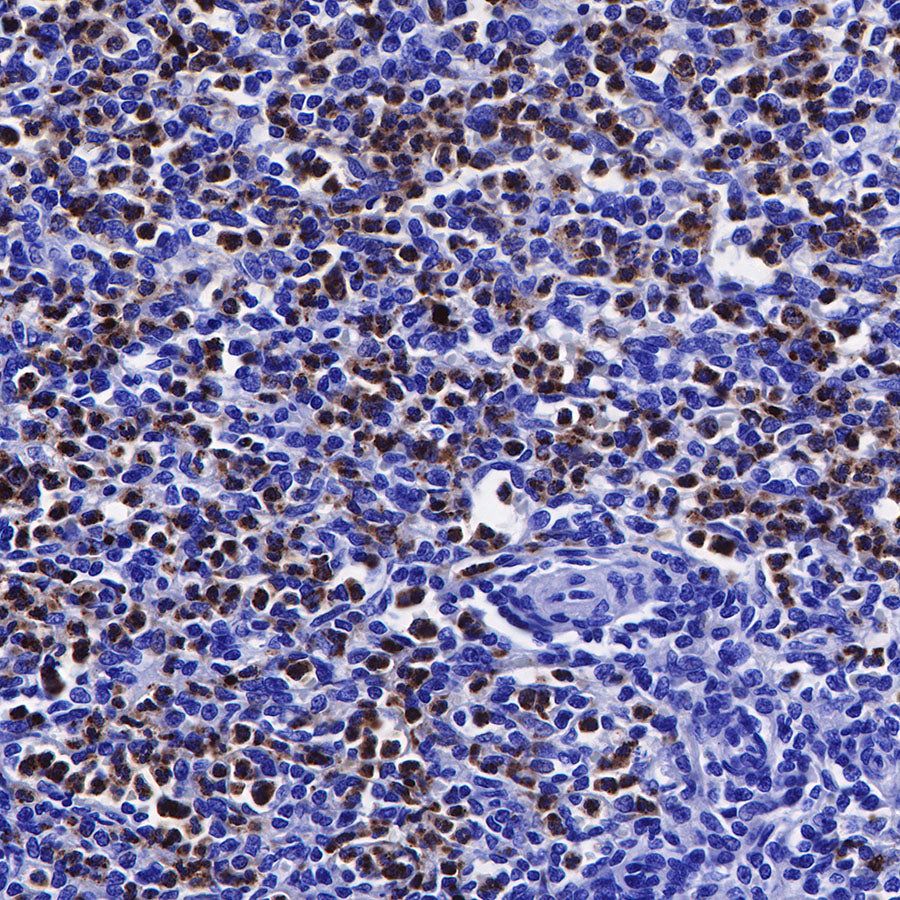

Immunohistochemistry

IHC shows positive staining in paraffin-embedded human spleen. Anti-Lysozyme antibody was used at 1/100 dilution, followed by a HRP Polymer for Mouse & Rabbit IgG (ready to use). Counterstained with hematoxylin. Heat mediated antigen retrieval with Tris/EDTA buffer pH9.0 was performed before commencing with IHC staining protocol.